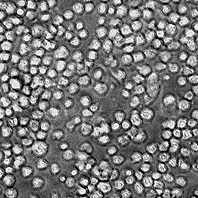

Морфология: лимфобластоподобная

Способ культивирования: суспензионный